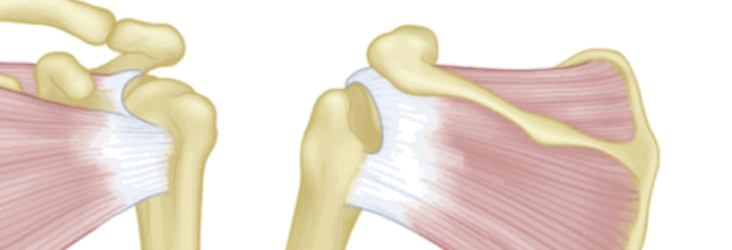

按照损伤程度分为部分撕裂( MR准确性>85% )和完全撕裂(MR准确性>95% )。

部分撕裂按照受损部位又分为滑囊面、关节面及肌腱内撕裂,在MRI上可以清晰的看到其受损部位。按照损伤深度分为1级:撕裂深度小于3mm,2级:撕裂深度在3-6mm,3级:撕裂深度大于6mm。

全层撕裂按照范围分为小撕裂:撕裂口<1cm,中撕裂:撕裂口1-3cm,大撕裂:撕裂口3-5cm,巨大撕裂:撕裂口>5cm。高清晰度的MRI是可以测定撕裂范围的。

按照撕裂的形状又分为新月形撕裂、U形撕裂、L形撕裂、倒L形撕裂、巨大回缩性/不可移动性撕裂。想要判断损伤的形状需要在MRI上利用多个平面、多张照片来分析。